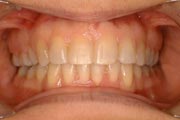

Crowding

After